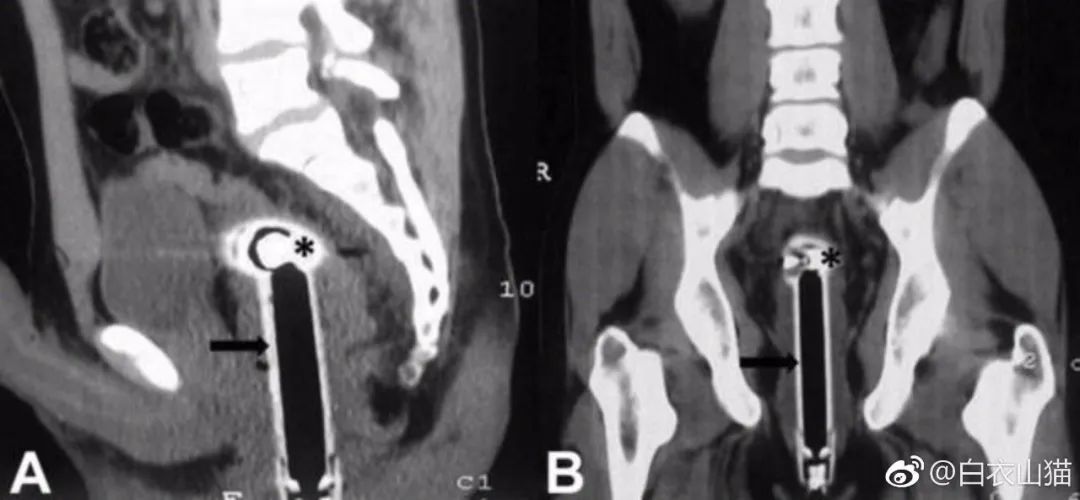

上面是近年医院里的一个病人,也是乙状结肠新鲜穿孔。医生给他开腹手术,从腹腔里取出来的5条泥鳅和一条黄鳝。

该病人提供的病史,是自己把活泥鳅和黄鳝生吞下去所导致。其实,医生一看泥鳅和黄鳝的颜色以及肠穿孔的部位,就知道怎么回事了。